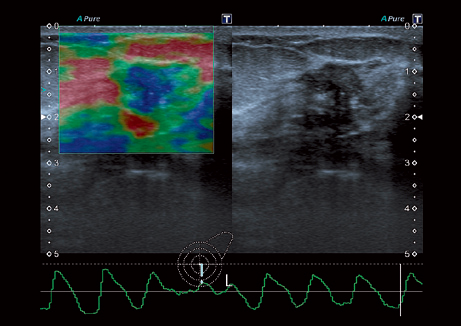

• Эластография

• Специальная фильтрационная технология выявления микрокальцинатов в молочной железе MicroPure;

• Прецизионная визуализация (Precision Imaging) для послойного дифференцирования тканевых структур и высокой детализации;